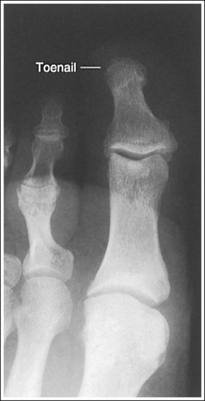

• Detecting toe rotation. Toe rotation is controlled by the position of the foot. Take a few minutes to study a toe skeleton and note that in an AP projection, concavity of the midshaft of the proximal phalanx is equal on both sides. Also, note that the posterior (plantar) surface of the proximal phalanx demonstrates more concavity than the anterior (dorsal) surface. As the skeleton is rotated medially or laterally, the amount of concavity increases on the side toward which the posterior surface is rotated, whereas the side toward which the anterior surface is rotated demonstrates less concavity. The same observations can be made about the soft tissue that surrounds the phalanges. More soft tissue thickness is present on the posterior surface than the anterior surface, so the side demonstrating the greatest soft tissue width on an image will be the side toward which the posterior surface is rotated. Look for this midshaft concavity and soft tissue width variation to indicate rotation on an AP axial toe projection. With lateral toe rotation, phalangeal soft tissue width and midshaft concavity are greater on the side positioned away from the lateral foot surface (see Image 1). With medial toe rotation, phalangeal soft tissue width and midshaft concavity are greater on the side positioned away from the medial foot surface (see Image 2). If the patient's toenail is visualized, which is often the case with the first toe, it can also be used to determine the direction of toe rotation. The nail rotates in the same direction as the foot.